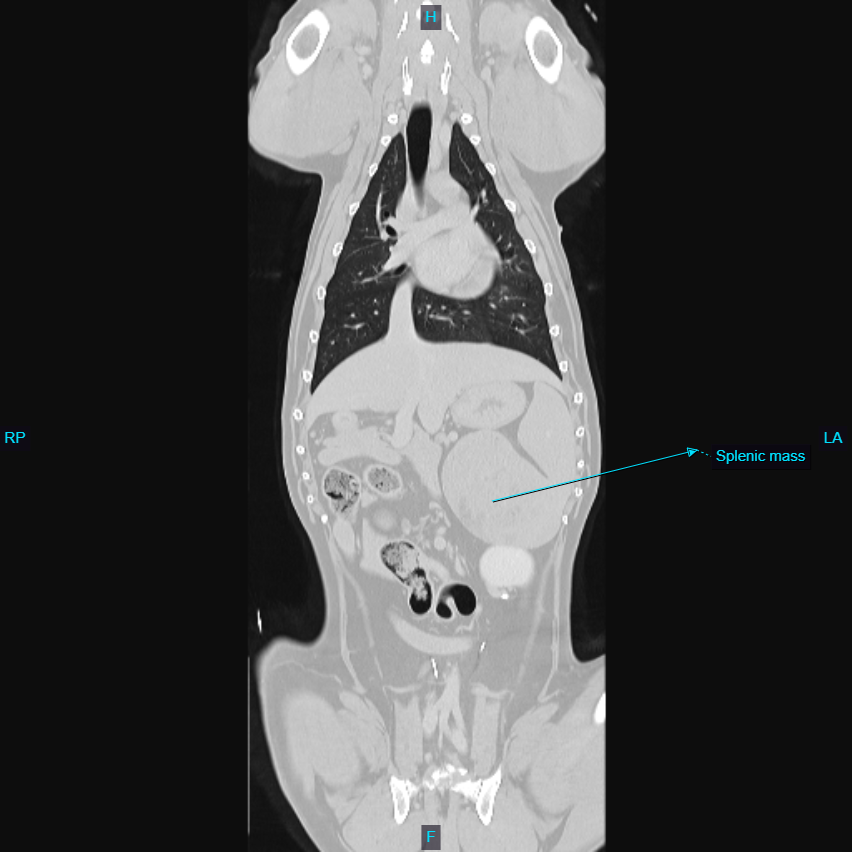

Oakley is now an 11 yo FS Lab. She presented in November for a splenic mass and suspected metastatic lung nodule. She was asymptomatic at home, other than she had vomited once and not eaten well for a few days. She presented through outpatient ultrasound with Dr. Sepulveda, who identified a splenic mass. Radiographs of the chest were taken, and found one solitary, approximately 2cm mass in the right caudal lung field, but no other changes. While it could have been a spread from the splenic mass, typically, we see more than one nodule, especially at 2cm in size. The owner wanted to give her every chance, so a CT was performed immediately before surgery, where just one nodule was confirmed (see pic – one of pulmonary nodule, one of splenic mass). She was taken to surgery with Dr. MacDougall and her spleen was removed, with biopsy results coming back about a week later as a myelolipoma, which is not cancer! The owner elected at first to monitor the nodule in her chest (in the accessory lung lobe). Radiographs taken about 3 months later showed about 50% increase in this pulmonary nodule, but no additional nodules or changes in her lung. The owner elected to allow Dr. MacDougall to take the lung nodule out via right lateral thoracotomy (removal of accessory lung lobe), and a grade 1 pulmonary carcinoma (removed with clean margins) was found on biopsy. This can potentially spread over time, but her prognosis is good. The owner was thrilled at her second chance at life, since she is in excellent health and still loves to walk, swim, and play. She is one of our perfect patients!